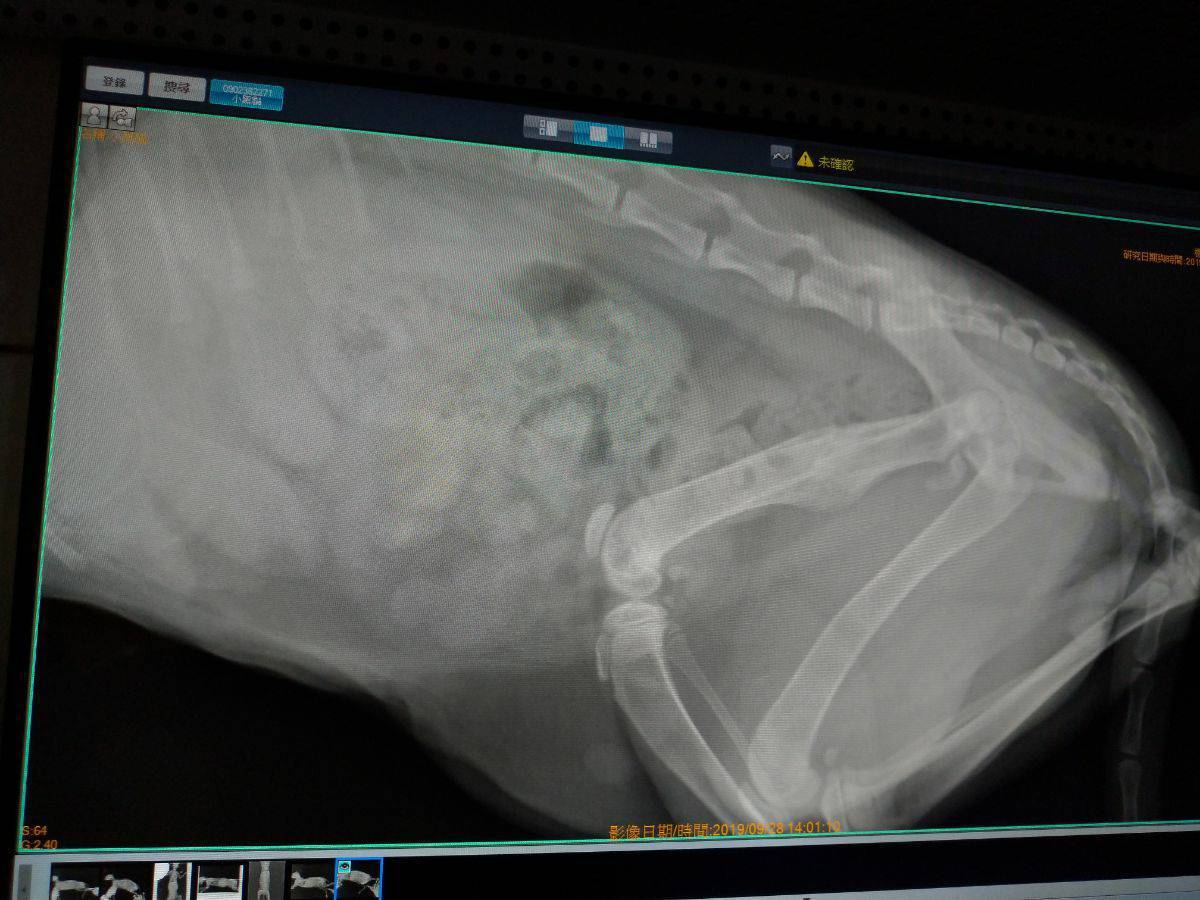

醫生初步看到X光片說小黑黑疑似橫隔赫尼亞,會先打針看看狀況,明天在拍一次X光片再研究是否確診,是否需要動手術,手術費用是一萬多。

而至於右後腿的骨折處,手術費也是一萬多,醫生有建議若醫藥費過高可以考慮只做赫尼亞,因為小黑黑是幼貓復原能力較好,會自行在受傷骨折處修復,只是以後走路會一跛一跛。

我比較擔心,小黑黑是幼貓,跛腳對浪貓影響會不會生存競爭力?抱歉,說很多,我是新手,不知道怎麼表達完整,謝謝您撥空閱讀,感恩!動物近況說明: 住院後確診為橫隔赫尼亞,右後大腿骨骨折,肝臟自橫隔破洞處滑入胸腔,壓迫大部份左肺,小部份右肺,肝臟並有發炎腫大現象,經醫生開刀處理及投藥治療後,左肺塌陷部份仍然沒有恢復,可能功能喪失,右腿骨折處由貓咪自體恢復,橫隔赫尼亞病況已經痊癒。